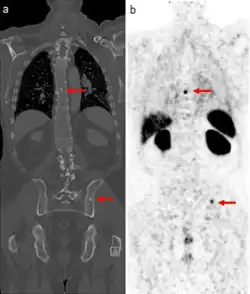

Gallium DOTA scans

68Ga DOTA conjugated peptides (including 68Ga DOTA-TATE, DOTA-TOC and DOTA-NOC) are used in positron emission tomography (PET) imaging of neuroendocrine tumours (NETs). The scan is similar to the SPECT octreotide scan in that an octreotide-based somatostatin analogue (such as edotreotide) is used as the radioligand, and there are similar indications and uses as octreotide scans, however image quality is significantly improved.[33] Somatostatin receptors are overexpressed in many NETs, so that the 68Ga DOTA conjugated peptide is preferentially taken up in these locations, and visualised on the scan.[34] As well as diagnosis and staging of NETs, 68Ga DOTA conjugated peptide imaging may be used for planning and dosimetry in preparation for lutetium-177 or yttrium-90 DOTA therapy.[35][36]